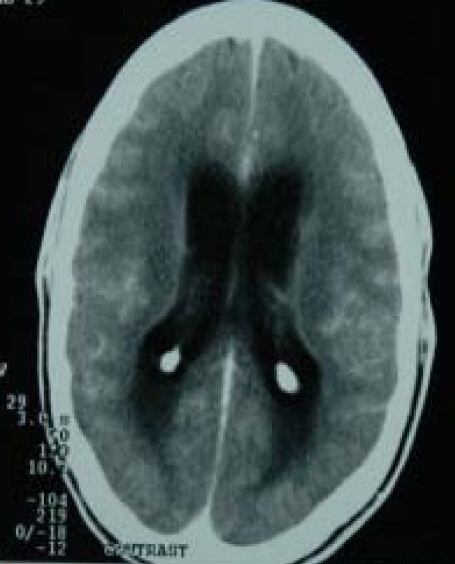

Komolafe, M., Sunmonu, T., Esan, O. · CC BY 2.0 · source

Diagnosis integrates cerebrospinal fluid analysis, neuroradiology, microbiology, and molecular assays developed at centers including Stanford University School of Medicine and Harvard Medical School. Cerebrospinal fluid profiles commonly show lymphocytic pleocytosis, elevated protein, and low glucose, patterns referenced in textbooks used at Yale School of Medicine and University of Toronto. Neuroimaging with magnetic resonance imaging or computed tomography, standardized in departments at UCSF Medical Center and University College Hospital, may reveal basilar enhancement, tuberculomas, or hydrocephalus. Microbiological confirmation uses smear microscopy, culture techniques from laboratories like Mérieux affiliates, and nucleic acid amplification tests exemplified by assays promoted by Foundation for Innovative New Diagnostics; diagnostic sensitivity and specificity have been evaluated in multicenter studies funded by agencies such as National Institutes of Health.